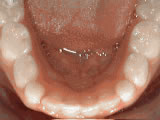

Missing lateral incisors

missing lateral incisors beforeBefore

missing lateral incisors afterAfter

This patient's lateral incisors were congenitally missing. She had braces for 20 months to move the teeth into their correct positions, then the missing teeth were replaced with bonded "Maryland" bridges.